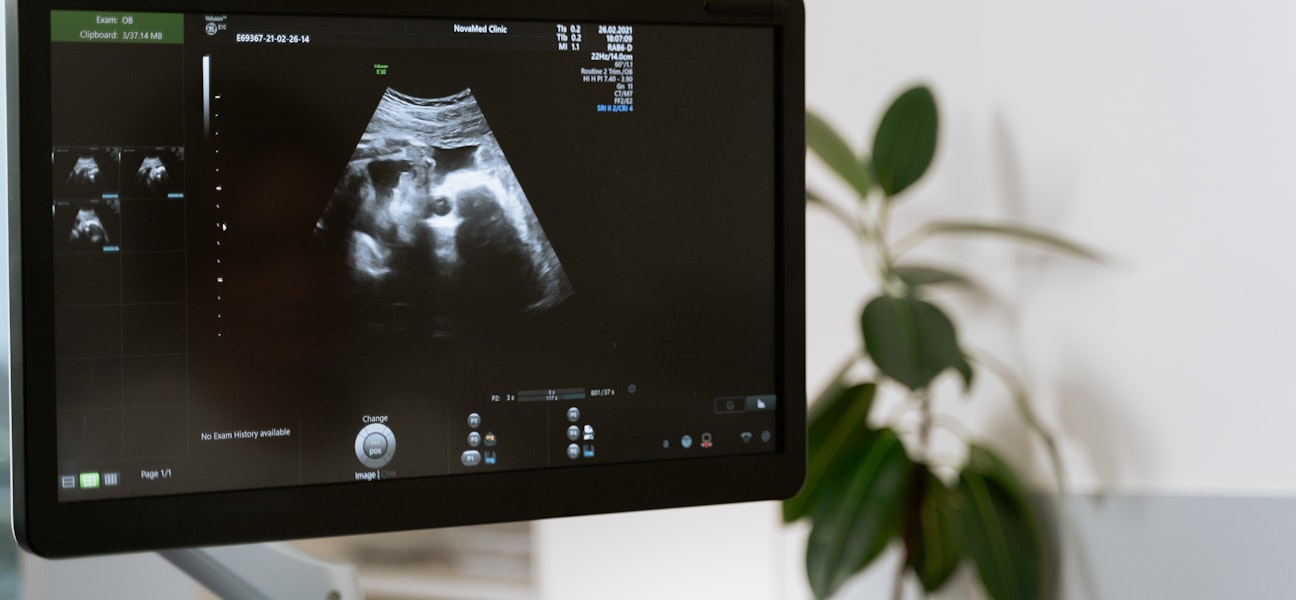

Le principe est simple : une sonde émettrice-réceptrice, posée sur votre peau, envoie des ondes ultrasonores qui traversent les tissus et rebondissent sur les organes. Ces échos sont convertis en images en temps réel sur un écran, ce qui permet au radiologue d'analyser la forme, la taille et la structure de vos organes abdominaux.

L'échographie abdominale fait partie de la famille plus large des échographies pratiquées en imagerie médicale, qui comprend également les échographies obstétricales, musculosquelettiques ou thyroïdiennes.